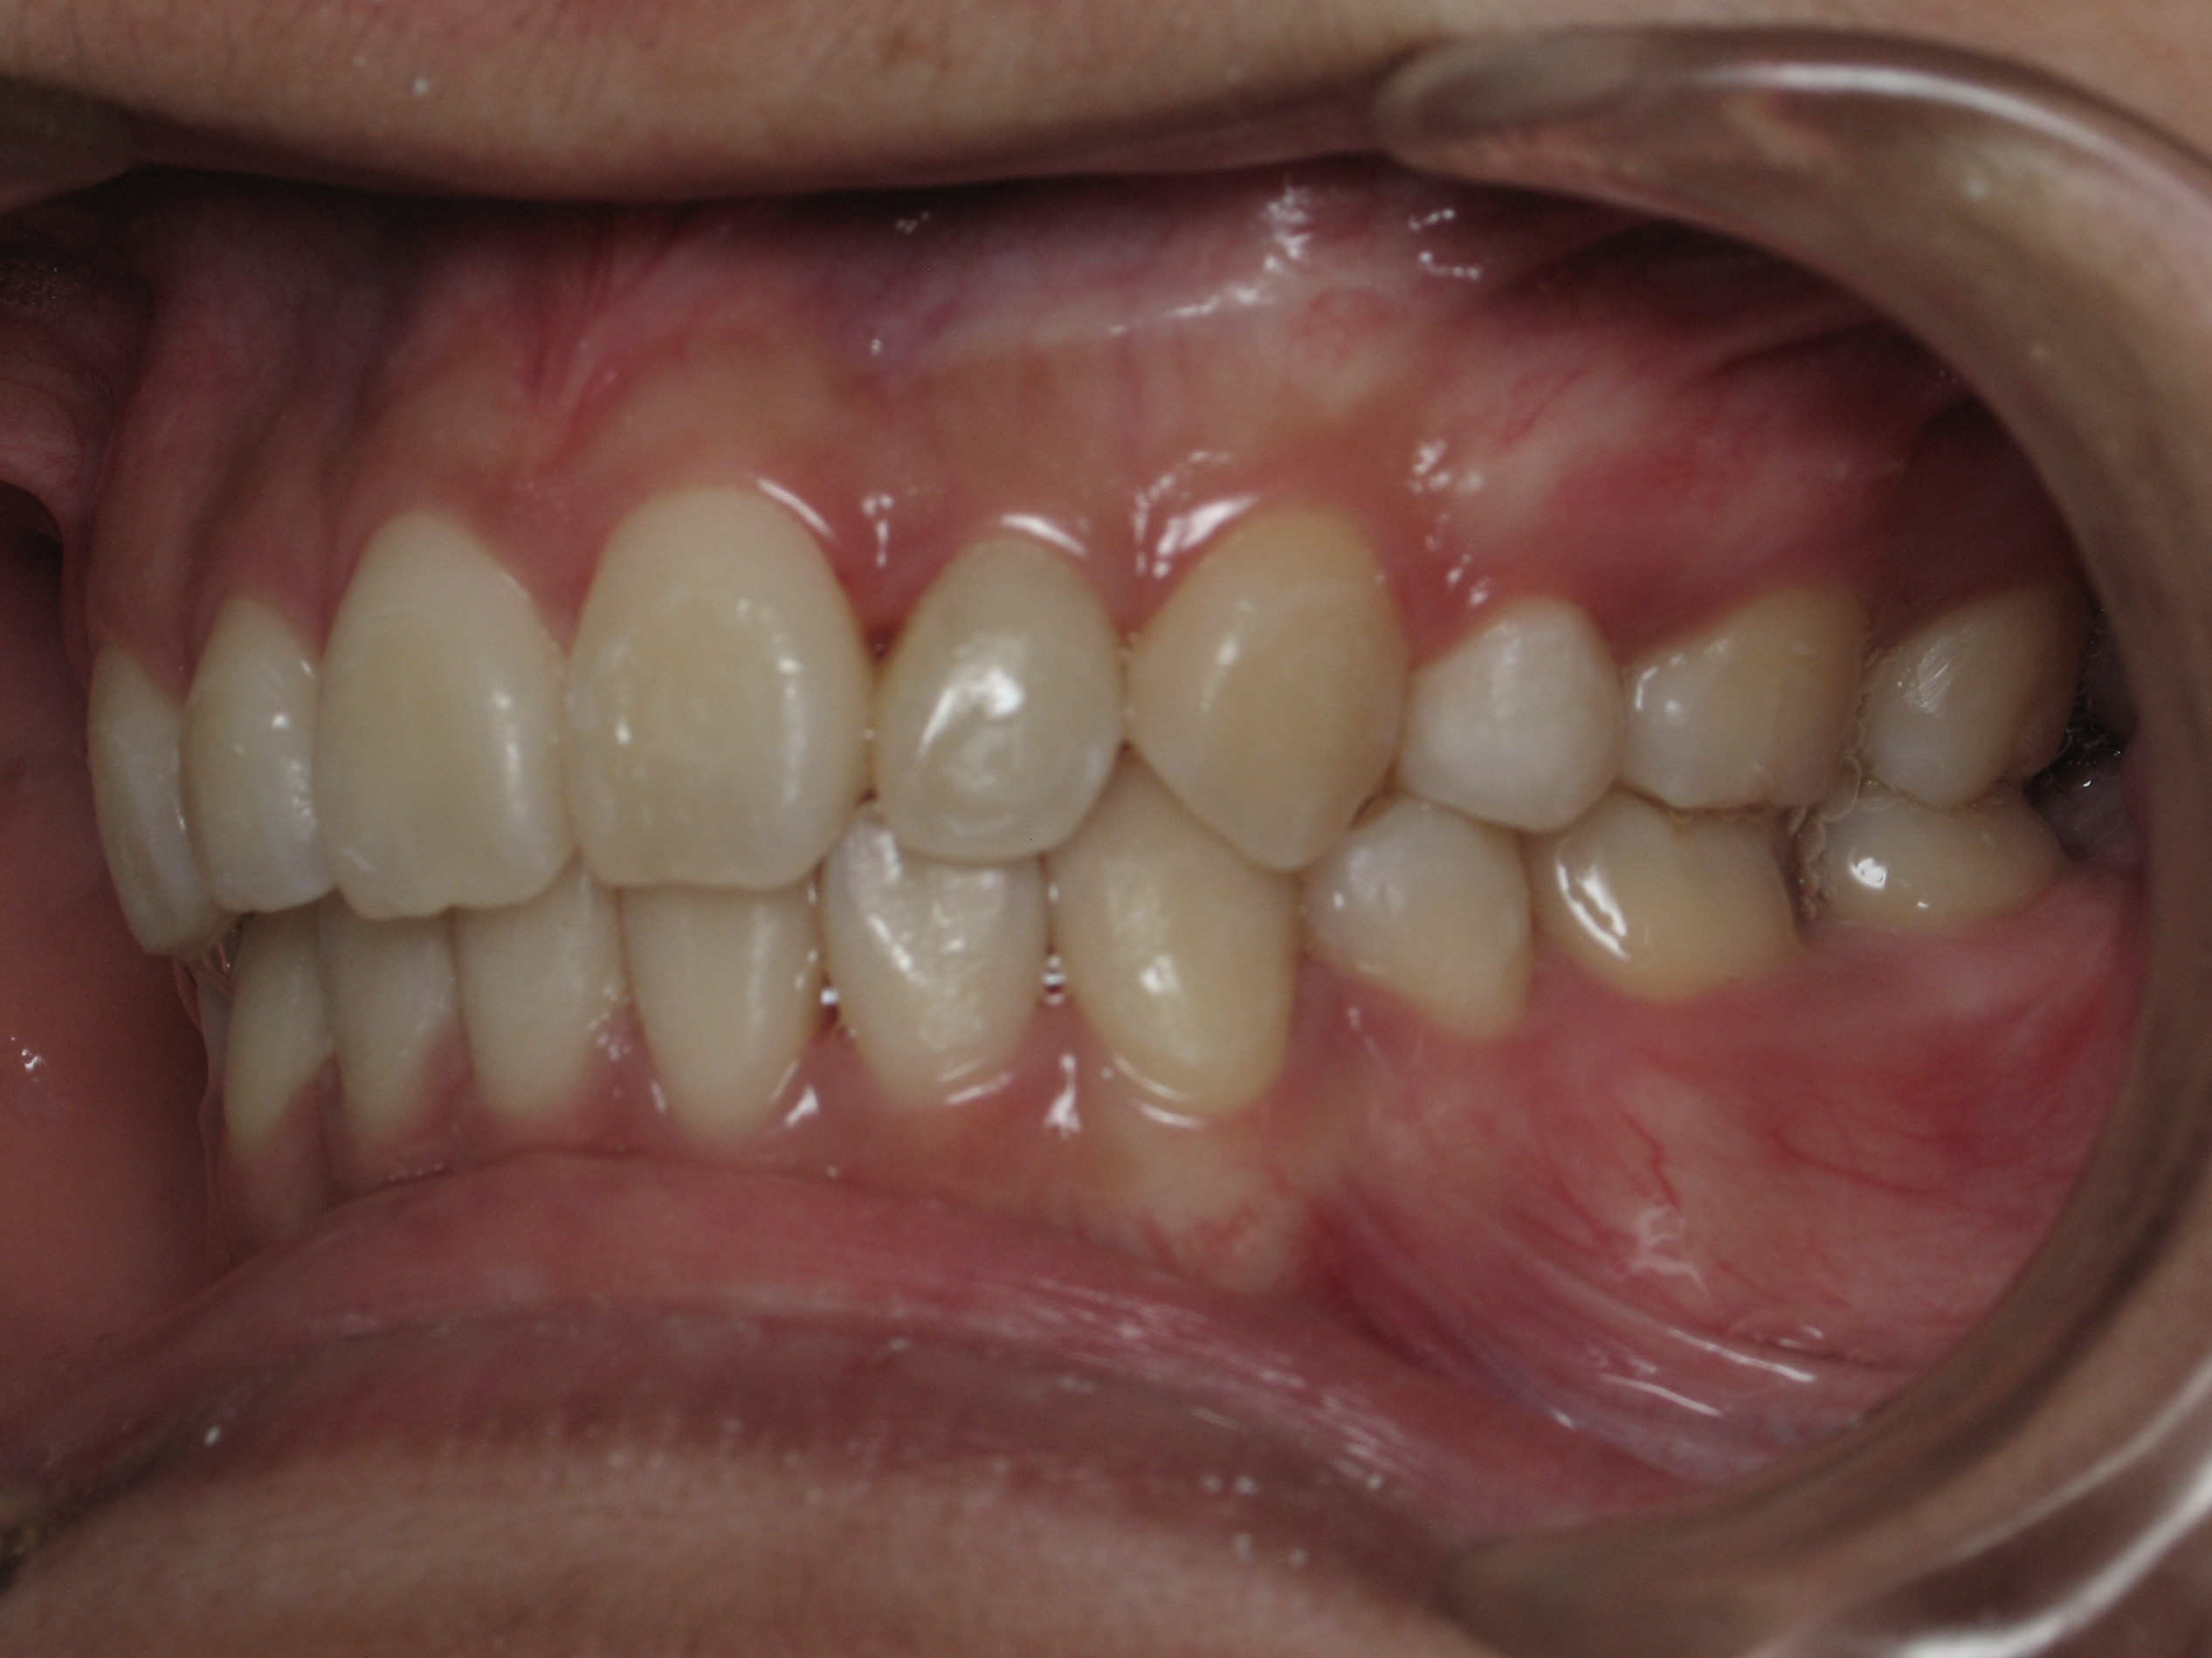

Smile Gallery

Orthodontic Treatment X-ray - Before

After Series of Teeth Extractions, Upper Left Canine Unerupted.

Ready to Start Ortho Treatment

Orthodontic Treatment X-ray - After